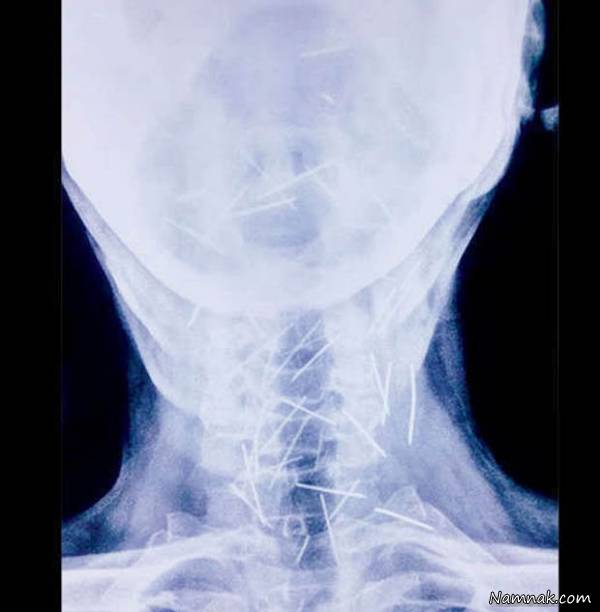

عکس های محل قرار گرفتن سوزن داخل گلوی بیمار

دکتر "لالیتا موهان" می گوید:برای من عجیب و غیر قابل باور است که بیمار با وجود این تعداد جسم تیز در بدنش دچاره آسیب جدی نشده است . درحقیقت برای من خارج کردن این تعداد سوزن از بدن بیمار کاری چالش برانگیز بود چرا که بسیاری از سوزن ها در بخش حساسی قرار داشتند، مری و حتی شریان کاروتید که اکسیژن را به مغز حمل می کرد پر بود از سوزن .

آقای میتا به دلیل دیابت و درد شدیدی که در پایش احساس می کرد به بیمارستان مراجعه کرد غافل از اینکه وضعیت نامناسب جسمی او ناشی از وجود بیش از 100 سوزنداخل بدنش بود.آزمایشات و عکسبرداری ها نشان داد که تعداد زیادی سوزن در قسمتهای مختلف بدن این مرد هندی قرار دارد مردی که ادعا میکرد به هیچ وجه نمی دانند چه طور سوزن ها وارد بدنش شده اند.